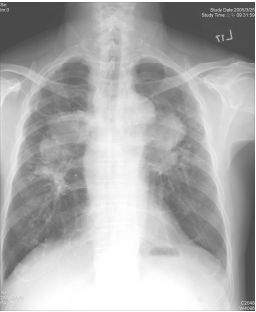

27.葉先生,74 歲,吸菸多年,且有慢性咳嗽病史,因發燒、呼吸喘、咳嗽、濃痰至醫院求診。 胸部 X-光顯示如右圖。下列何者為最有可能的臆斷? (A) 肺炎 (B) 肺癌 (C) 肺結核 (D) 塵肺症